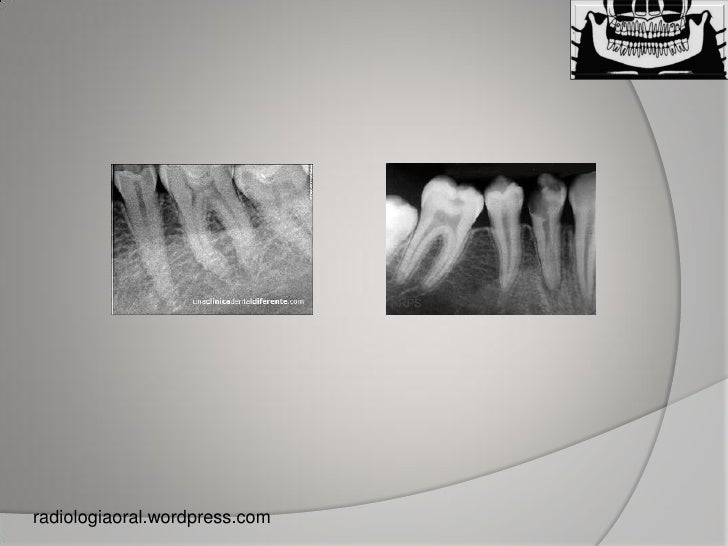

Dental radiographs. (a) Bitewing. (b) Periapical. (c) Occlusal. (d